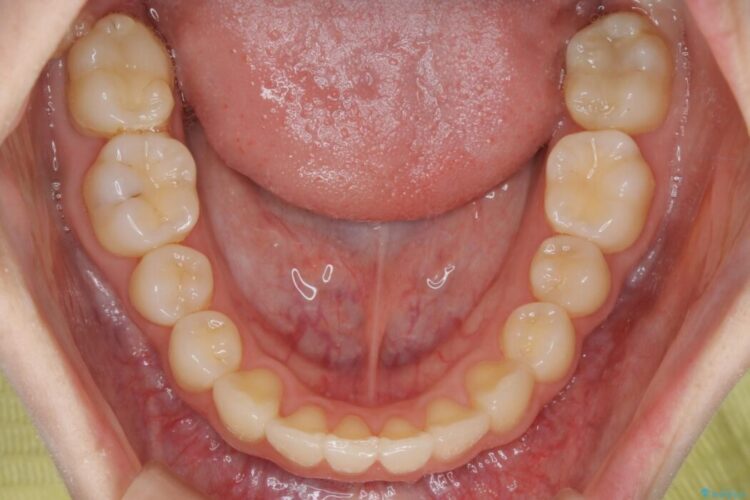

【20代女性】ブライダルに向けた矯正できれいなスマイルラインへ

- 患者様:20代女性

- 治療期間:1年10ヶ月

- 矯正装置:インビザライン コンプリヘンシブパッケージ

笑った時に見える歯並びをきれいにしたいとの主訴で来院されました。

ガタつきの度合いから抜歯は不要と判断しましたので、マイクロインプラントを用いて歯全体を遠心移動させていくことでねじれや噛み合わせのズレを改善していく計画を立てました。